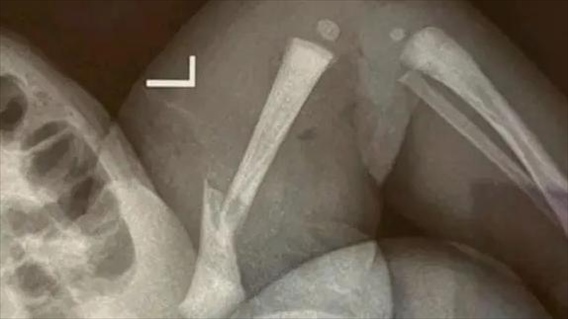

·江蘇靖江新生兒骨折家長(zhǎng)質(zhì)疑系醫(yī)療事故,靖江市人民醫(yī)院:手法不熟導(dǎo)致。